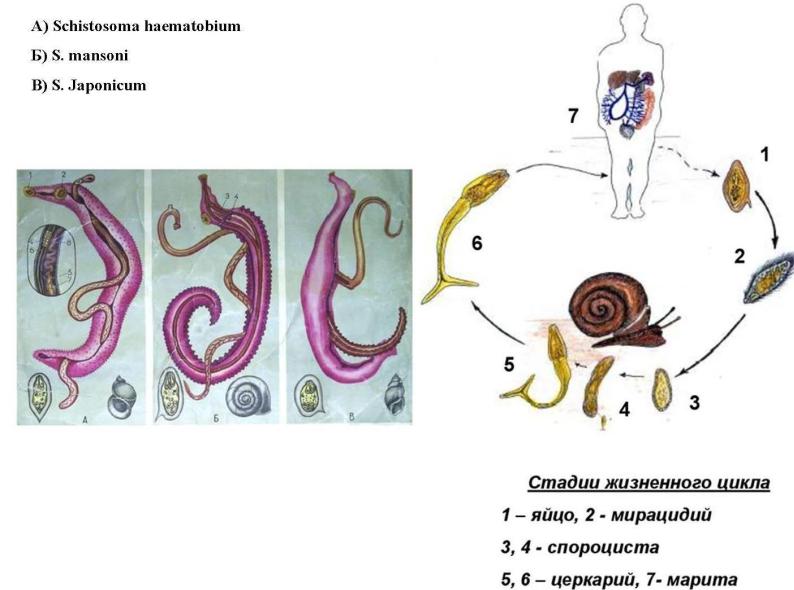

Шистосомоз: что нужно знать о паразитах